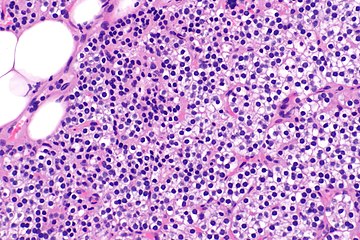

Parathyroid hyperplasia high mag.

Parathyroid glands are normally composed of chief cells, adipocytes and scattered oxyphil cells.[27][14] Chief cells are thought to be responsible for the production, storage and secretion of parathyroid hormone. These cells appear light and dark with a prominent Golgi body and endoplasmic reticulum. In electron micrographs, secretory vesicles can be seen in and around the Golgi and at the cell membrane. These cells also contain prominent cytoplasmic adipose.[27][14] Upon onset of hyperplasia these cells are described as having a nodular pattern with enlargement of protein synthesis machinery such as the endoplasmic reticulum and Golgi. Increased secretory vesicles are seen and decreased intercellular fat is characteristic.[27][24] Oxyphil cells also appear hyperplasic however, these cells are much less prominent.[citation needed]